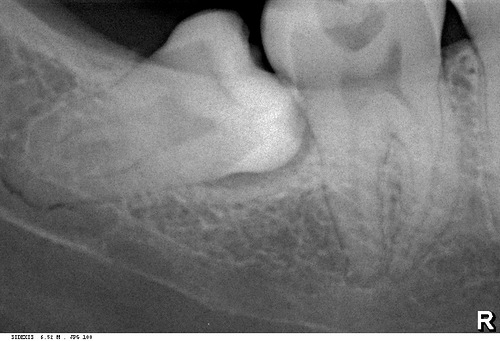

Далее, приступаем к удалению. Неплохо было бы ознакомиться со снимками, для начала — ведь большая часть зуба находится, как известно, вне нашего зрения и видна только на рентгенограммах.

Во-первых, панорамный снимок — штука, сильно искажающая пространственное соотношение тканей и структур. Возьмите два листа бумаги с текстом с обеих сторон, сложите их вместе и посмотрите на просвет. Удается ли прочитать текст? Вот ортопантомограмма — примерно, то же самое. Другими словами, сказать по ортопантомограмме о соотношении верхнечелюстной пазухи и корней верхних зубов, равно как и о положении корней восьмерок и нижнечелюстного канала ДОСТОВЕРНО НЕЛЬЗЯ! Поэтому, для такой точной работы как дентальная имплантация, нам нужна компьютерная томография.

То же самое касается и нижнечелюстного нерва и восьмерок. Сделав компьютерную томографию мы убедимся, что нижнечелюстной нерв находится гораздо более язычно, нежели корень зуба. А на снимке они, нередко накладываются друг на друга создавая иллюзию пересечения.